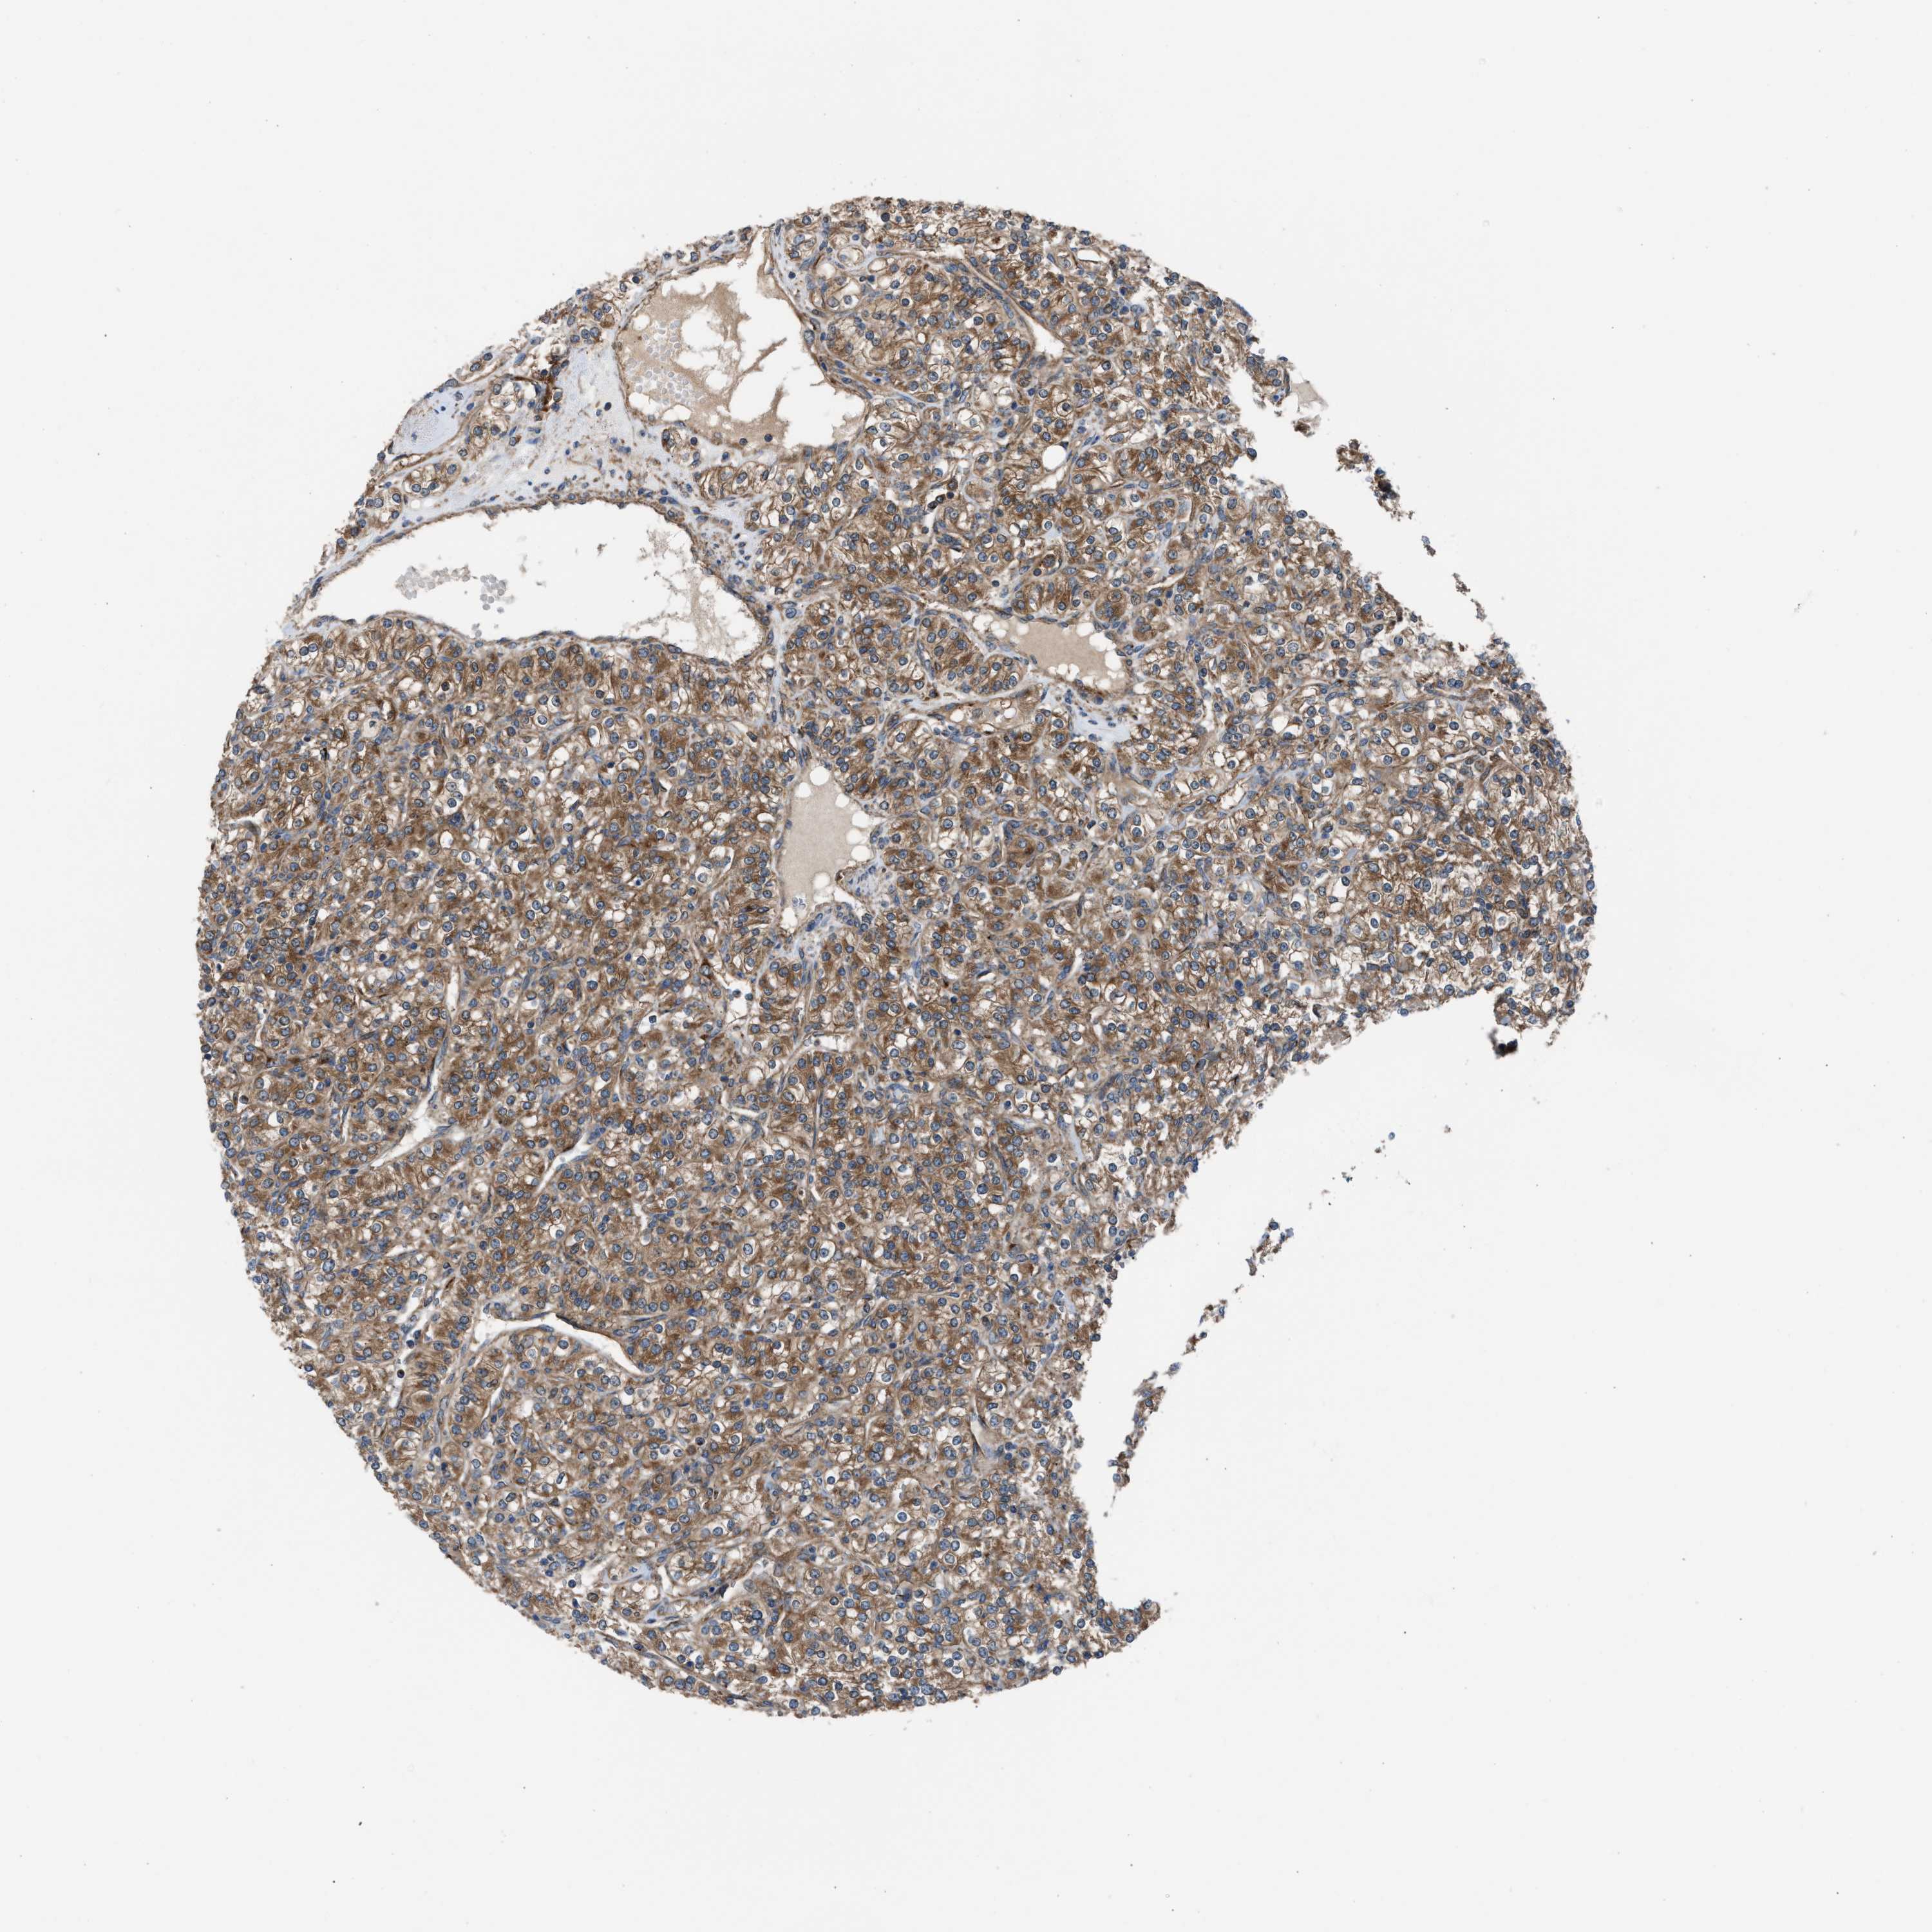

KIDNEY RENAL CLEAR CELL CARCINOMA (VALIDATION) - Interactive survival scatter ploti

The Survival Scatter plot shows the clinical status (i.e. dead or alive) for all individuals in the patient cohort, based on the same data that underlies the corresponding Kaplan-Meier plots. Patients that are alive at last time for follow-up are shown in blue and patients who have died during the study are shown in red.

The x-axis shows the expression levels (FPKM) of the investigated gene in the tumor tissue at the time of diagnosis. The y-axis shows the follow-up time after diagnosis (years). Both axes are complimented with kernel density curves demonstrating the data density over the axes. The top density plot shows the expression levels (FPKM) distribution among dead (red) and alive patients (blue). The right density plot shows the data density of the survived years of dead patients with high and low expression levels respectively, stratified using the cutoff indicated by the vertical dashed line through the Survival Scatter plot. This cutoff is automatically defined based on the FPKM cutoff that minimizes the p-score. The cutoff can be changed by dragging the vertical line or by entering a cutoff value in the square labeled "Current cut-off".

Under the Survival Scatter plot the p-score landscape (black curve; left axis) is shown together with dead median separation (red curve; right axis). Dead median separation is the difference in median mRNA expression between patients who have died with high and low expression, respectively. It is calculated as follows: median FPKM expression of dead patients with high expression - median FPKM expression of dead patients with low expression. This is intended to aid the user in visually exploring custom cutoffs and the associated p-scores and dead median separation.

Individual patient data is displayed and can be filtered by clicking on one or more of the category buttons on the top of the page. Categories describing expression level and patient information include: high, low, alive, dead, female, male and tumor stages. The scale of the x-axis can be toggled between linear and log-scale by clicking on the "x log" button. Mouse-over function shows TCGA ID, patient information and mRNA expression (FPKM) for each patient.

& Survival analysisi

Kaplan-Meier plots summarize results from analysis of correlation between mRNA expression level and patient survival. Patients were divided based on level of expression into one of the two groups "low" (under cut off) or "high" (over cut off). X-axis shows time for survival (years) and y-axis shows the probability of survival, where 1.0 corresponds to 100 percent.

ZNF614 is validated prognostic, high expression is favorable in Kidney Renal Clear Cell Carcinoma (validation)

Best expression cut offi

Based on the FPKM value of each gene, patients were classified into two groups and association between prognosis (survival) and gene expression (FPKM) was examined. The best expression cut-off refers the FPKM value that yields maximal difference with regard to survival between the two groups at the lowest log-rank P-value. Best expression cut-off was selected based on survival analysis .

When clicking on this number, the vertical dashed line indicating cut-off, the interactive survival plot, and the Kaplan-Meier curve will be adjusted to show results based on the best expression cut-off.

: 5.61

TCGA RNA samplesi

RNA-seq data is reported as average FPKM (number Fragments Per Kilobase of exon per Million reads), generated by the The Cancer Genome Atlas (TCGA) .

Normal distribution across the dataset is visualized with box plots, shown as median and 25th and 75th percentiles. Points are displayed as outliers if they are above or below 1.5 times the interquartile range. FPKM values of the individual samples are presented next to the box plot.

Average pTPM 5.4

Number of samples 100